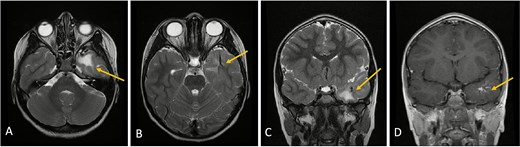

Axial lower cut (A)/axial higher cut (B)/coronal (C) T2-weighted MRI of the brain shows a prominent area of T2 hyperintensity (arrow) in the white matter of the left anterior temporal lobe, adjacent to the DVA. The DVA itself is clearly delineated on the contrasted sequence (D) and its draining veins contribute to the local anatomy (arrow). (E) Axial FLAIR (fluid-attenuated inversion recovery) highlights the abnormal hyperintensity in the left anterior temporal lobe white matter (arrow), suppressing the cerebrospinal fluid signal and making the white matter changes more conspicuous. This represents chronic changes such as gliosis or edema.

MRI with and without gadolinium contrast identified a vascular lesion consistent with a DVA in the left anterior temporal lobe. This showed typical caput medusae venous morphology. Adjacent white matter T2/FLAIR hyperintensities were present without diffusion restriction or blooming on gradient-echo sequences. No abnormal contrast enhancement was noted, and major venous sinuses were patent (Figs 1 and 2).